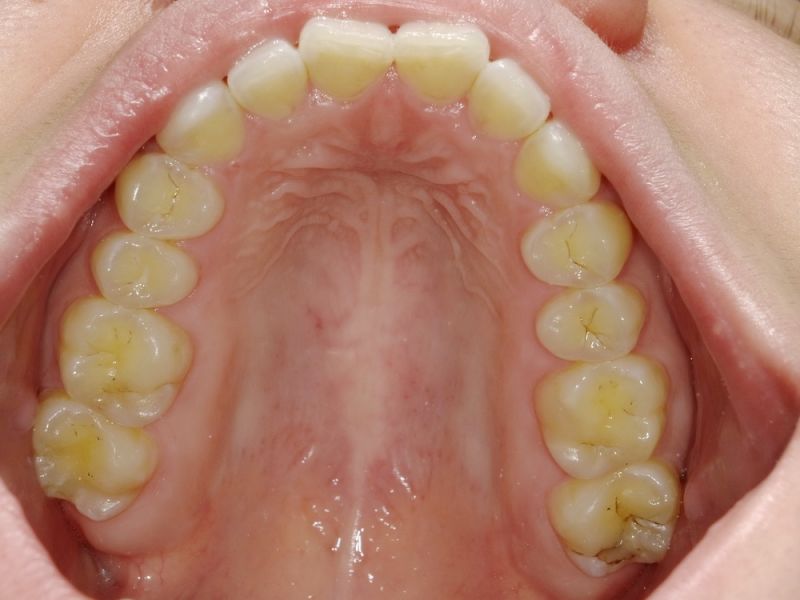

Ganz aktuell war die Patientin bei einer Hauszahnärztin, die auf die Idee kam der Patientin zwei Eckzahnfacetten im Oberkiefer zu installieren, mit dem Ergebnis, dass die Beschwerden der Patienti sich nochmals verschlechtert haben.

Es bestehen vorrangig Beschwerden im Berech des Halses hinter und unter dem linken Unterkieferwinkel und im Bereich des linken Ohres. Weiterhin auch im rechten Schläfenbereich nach unten hinten ausstrahlend.

Der Biss gesucht wird, der Biss passe nicht, seit ein paar Jahren

Zähneknirschen/pressen